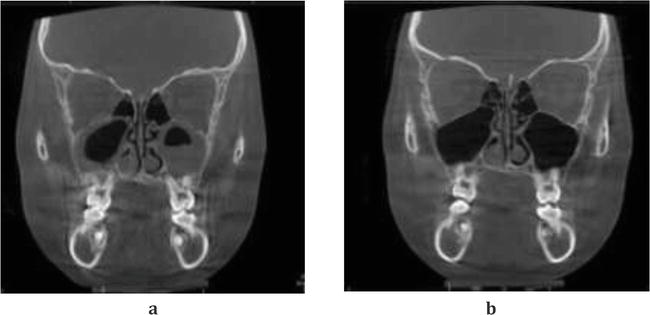

Segmental lefort expansion can also help the tongue reposition correctly, further reducing tension.

Segmental lefort expansion can also significantly improve nasal breathing due to expansion and widening of the nasal cavity.

CBCT SCAN USES

CBCT scans are useful for:

Planning your custom implants in the future

Jaw surgery planning

Airway assessment

Bite analysis

Bone structure evaluation in relation to soft tissue